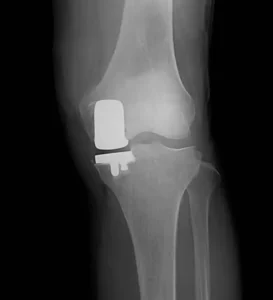

人工ひざ関節単顆置換術 UKA

- 手術の目的

内側または外側のいずれかに限局した関節の摩耗に対して、可能な限り健康な関節を温存しながら痛みを取り除き、日常生活を改善することを目的とします。

- 手術の内容

- 前十字靭帯(ACL)は温存され、関節本来の自然な動きが維持されます。

- 脛骨の骨切りでは、ナビゲーションシステムを用いて患者様個々の骨構造に合わせた最適な角度を調整し、インプラントの安定性を高めます。

- 当院の特色

- 脛骨の骨切りにナビゲーションを活用し、患者様ごとの骨形態に合わせて角度を微調整。

- 前十字靭帯を温存し、関節の自然な動きを維持。

- メリット

- 関節の自然な動きが維持される。

- 小切開手術のため、筋肉への侵襲が少なく、回復が早い。

- 脛骨の骨切りをナビゲーションで調整することで、患者さんのひざに合った角度が得られ、手術後の満足度が高い。